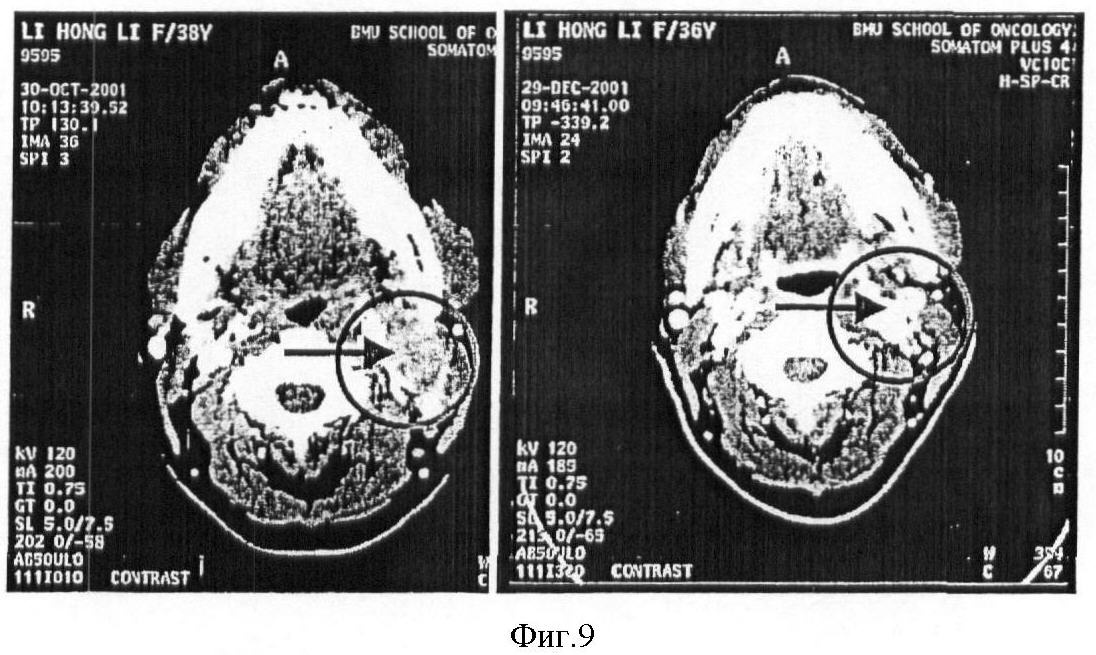

На I стадии клинических испытаний указанный рекомбинантный р53 аденовирус применяли для 12 пациентов с раком гортани средней и поздней степени. Спустя 31-36 месяц после этого лечения пациентов наблюдали повторно. Результаты показали, что применение указанного рекомбинантного аденовируса было в высшей степени безопасно. Ни у одного из 12 пациентов никаких рецидивов не наблюдалось. В настоящее время в течение 3 лет выживало только 44% таких пациентов, а частота послеоперационных рецидивов на протяжении 6-12 месяцев составляла 20%. Клинические испытания, проведенные для настоящего изобретения, показали, что указанный рекомбинант можно использовать не только при лечении новообразований, но также и для их предотвращения. Стадия II клинических испытаний проводится постоянно, начиная с 2001 года. Эффект проводимого лечения был очень многообещающим. Приведенные на фиг.9-13 результаты показывают, что рекомбинант по настоящему изобретению был также эффективен для лечения тех пациентов, которые были невосприимчивы к обычным методам лечения (химиотерапия и радиотерапия).

Фиг.9 (фото) представляет результаты компьютерной томографии, описывающие клинический эффект рекомбинанта р53 аденовируса при обработке им в случае рака носоглотки (фаза II). Левая фотография отражает картину до обработки, а правая – после нее (опухоль уменьшилась на 87%, отмечается некроз).

Клиническое действие рекомбинанта аденовируса р53 (рак носоглотки).

На фиг.9 показано, что рекомбинант аденовируса р53 был использован в клинических испытаниях рядом больниц, указанных управлением по пищевым продуктам и лекарственным средствам. Этот чертеж представляет также результаты компьютерной томографии пациента с раком носоглотки до и после обработки с использованием рекомбинанта аденовируса р53. Левая фотография отражает картину до обработки, а правая – после нее (опухоль уменьшилась на 87%, отмечается некроз). В клинических испытаниях участвовало более 60 пациентов, имеющих фазу II указанного заболевания. Клинический эффект лечения был значителен.